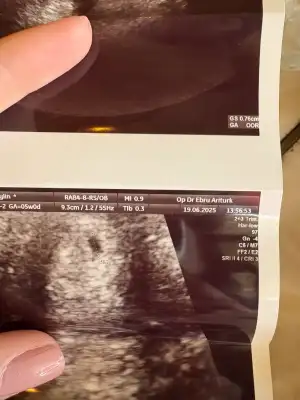

Merhaba kızlar, umarım hepimiz bebeklerimizi sağlıklı bir şekilde kucağımıza alırız. Benim sat 2 Mayıs. 4 Haziranda idrar testinde pozitif gördüm. 10 Haziranda (gece) kanda beta hcg 593, 12 haziranda (sabah) beta hcg 1509 olarak ölçüldü (2.5 günde 2.5 kat gibi artmış oldu). 14 haziranda ilk doktor kontrolüme gittiğimde keseyi gördük. Sata göre 6+1 olan gebeliğim ultrasonda 4+6 olarak hesaplandı. Doktorum geç döllenme olabilir ancak ilerleyen günlerde haftasını yakalayabilir, bir sonraki kontrolde tekrar hesaplarız hem de kalp atışını duyarız dedi. 23 haziranda 2. Kontrolüme gideceğim. Sata göre 7+3 olucak ancak bi önceki ultrason hesabına göre ise 6+1 olucak (eğer haftasını yakalamazsa). 23 haziranda kalp atışını duyar mıyım sizce?